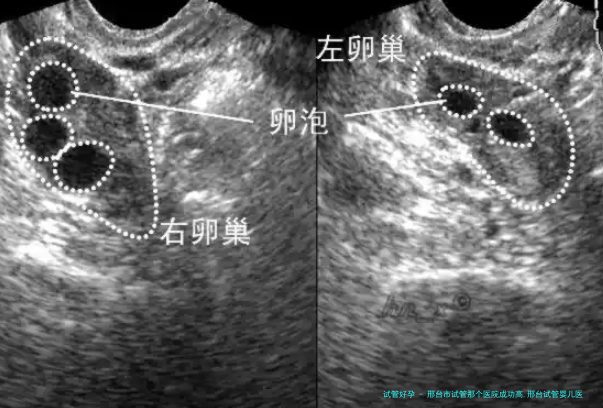

河北省人民医院引进了国内和国外先进的试管婴儿技术和设备,囊括辅助生育技术、胚胎培育系统等。这一些设备可以更准确地监测病人的生殖健康标准,提高受孕成功率并降低并发症出现风险。